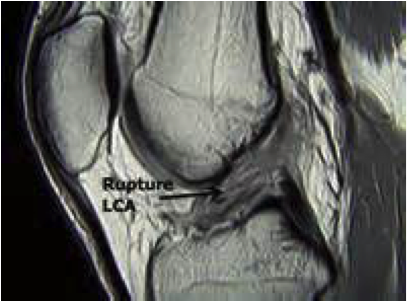

Lésion du Ligament Croisé Antéro Latéral (LCAE ou LCA)

Le diagnostic

Le diagnostic de rupture du ligament croisé antérieur (LCA) peut être évoqué dès l’accident.

Il est habituellement affirmé par l’examen clinique.

Quels sont les examens complémentaires nécessaires ?

Les examens complémentaires vont confirmer le diagnostic, et faire le bilan de lésions associées (ménisques, lésions ligamentaires) :

- Bilan d’imagerie : IRM, Arthroscanner.